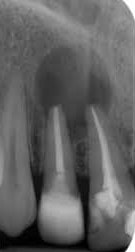

Gyökérfelszívódás

A gyökérfelszívódás a foggyökér megrövidülését jelenti. Tejfogazatban ez egy kívánatos reakció, mely a növekvő maradófog miatt jön létre. A maradófog hatására a tejfogak gyökere elkezd felszívódni, a tejfog meglazul, majd végül kiesik és helyét átveszi a megfelelő maradófog. Sajnos ez a folyamat maradófogazatban is megfigyelhető. Oka lehet fogakat ért baleset, trauma, súlyos fertőzés, de fogszabályozó kezeléseknél is előfordul. Ennek megfelelően a gyökérfelszívódások csoportosítása: belső - gyulladásos eredetű (pl.: fogbélgyulladás miatt), felületi (fogszabályozás során) és helyettesítő (balesetet szenvedett fogaknál).

Fogszabályozás során felületi, gyulladásmentes gyökérfelszívódás alakulhat ki. Fontos tisztában lenni azzal a ténnyel, hogy gyökérfelszívódás minden fogszabályozó kezelés során fellép, csupán oly kis mértékű, hogy nem lehet diagnosztizálni! A fogmozgatás miatt a foggyökerek csúcsa lekerekedik, majd a kezelés végén spontán helyreáll.

Ritkán, súlyos esetben a foggyökér jelentős megrövidülése jön létre. Ennek mértéke megjósolhatatlan, akár a fog meglazulásához, elvesztéséhez is vezethet. Legtöbbször 1-1 fogat érint, a generalizált, teljes fogazatot érintő gyökérfelszívódás extrém ritka.

Kialakulásának pontos oka még nem ismert, több faktor együttes jelenléte szükséges, és valószínűleg genetikai háttere is van. Hajlamosító tényező lehet a korábban balesetet szenvedett fog, vagy ha a kezelés során túl nagy erőkkel mozgatjuk a fogakat. Az önligírozó fogszabályzók helyes használatával ennek lehetősége minimalizálható.